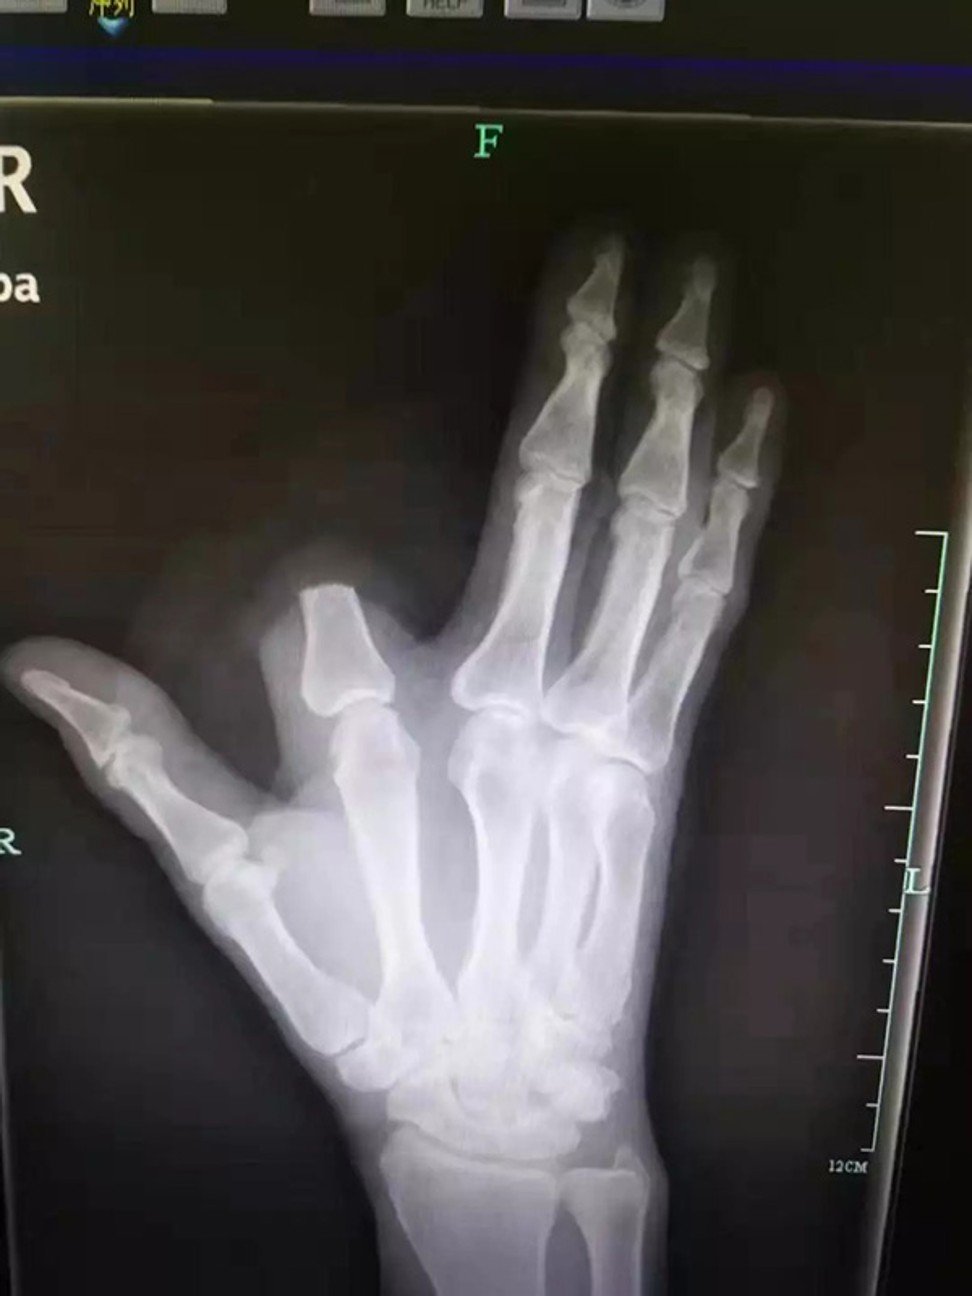

Ảnh chụp X-quang bàn tay bị chặt mất ngón trỏ của ông Zhang